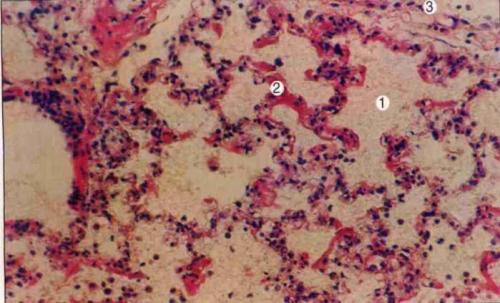

通过主诊医师的细致问诊、看诊、听诊,并结合专业仪器的检查结果,确定过敏性紫癜病人的病情程度以及病症分型,个人体质、免疫、血管、肾脏损害情况等。

结合患者自身情况,根据需求安排患者接受规范化检查,内容包括:血常规、尿常规、血管脆性检查、免疫检查、腹部B超检查、胃肠镜检查、肾穿刺检查等。